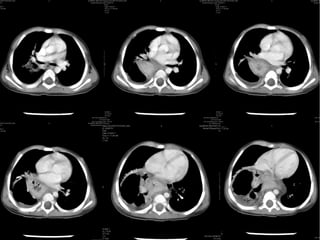

A 7-day-old boy with a

Morgagni hernia. a, b Anteroposterior

(a) and lateral (b) chest

radiographs show a poorly defined

right chest mass and right

upper lung atelectasis. c Sagittal

color Doppler sonogram of the

right chest obtained on the same

day shows herniation of the liver

(L) through an anterior foramen

of Morgagni hernia (arrows).

Note the abnormal course of the

hepatic vein and the difference

in echotexture of the intrathoracic

(T) and intraabdominal (A)

portions of the liver. d, e Sagittal

(d) and coronal (e) contrastenhanced

CT reconstructions

obtained the same day confirm

anterior liver (L) herniation

Hiatus hernia

A 7-day-old boywith a Morgagni hernia. a, b Anteroposterior (a) and lateral (b) chest radiographs show a poorly defined right chest mass and right upper lung atelectasis. c Sagittal color Doppler sonogram of the right chest obtained on the same day shows herniation of the liver (L) through an anterior foramen of Morgagni hernia (arrows). Note the abnormal course of the hepatic vein and the difference in echotexture of the intrathoracic (T) and intraabdominal (A) portions of the liver. d, e Sagittal (d) and coronal (e) contrastenhanced CT reconstructions obtained the same day confirm anterior liver (L) herniation